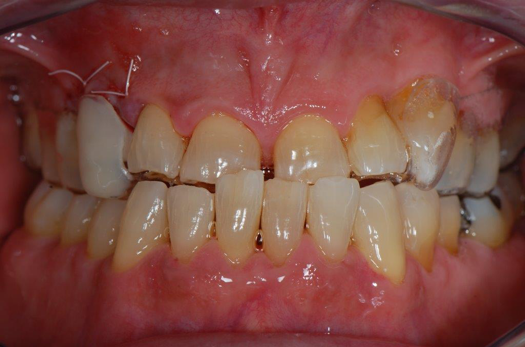

Fig 18. Preoperative image.

Figure 18

Occasionally dentists are presented with extreme challenges with long-term restorations and replacing missing teeth. Dentists must evaluate the patient's condition, develop optimum long-term oral health, and attempt to meet the patient's expectations. Figure 18 showed a class III malocclusion with deep bite, multiple abfractions, and less-than-ideal occlusal plane, but the patient wanted to replace his maxillary right canine only. A discussion with the patient regarding occlusal disharmonies and comprehensive recommendations for full-mouth rehabilitation revealed that the patient had a limited budget for dental care. The patient understood the ramifications of his comprehensive dental needs not being affordable. Decisions were made to atraumatically remove the maxillary right canine (Figure 19) and immediately place a ceramic dental implant (Figure 20). Polytetrafluoroethylene (PTFE) 4-0 sutures were placed to help support soft tissues, and then a full-arch Essix-style retainer with a flowable composite facial veneer was used to provide some esthetics during the patient's healing phase (Figure 21). The implant and the retainer were not to be in contactthe retainer may occlude with the opposing dentition and also be passive in relation to the ceramic implant.